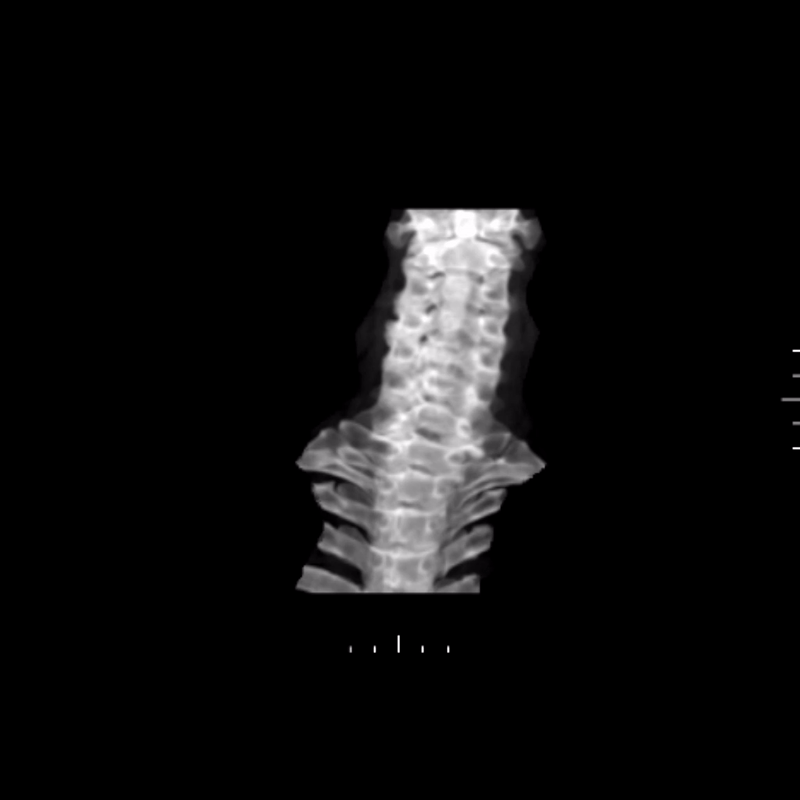

Using the CT dataset, a radiologic technologist processed the images to create a series of advanced visualizations that highlight the distribution of ossification and its relationship to surrounding anatomy. These images provide different perspectives of the cervical spine and help translate cross-sectional findings into more intuitive views.

Figure E: Grayscale rotational volume render of the spine.